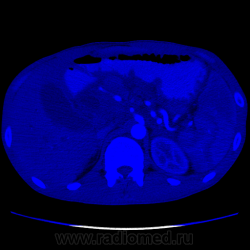

Видео крутит быстро. В головке плджелудочнгой железы кистозное образование с неравномерной толщины капсулой, наличием перегородок и солидного компонента. Печёночные желчные протоки, холедох значительно расширины. Вирсунгов проток расширен. Начальные отделы воротной вены сужены, возможно есть прорастание, не могу уследить. Итого: макрокистозная цистаденома (возможно уже цистаденокарцинома)

Не вижу, честно говоря, ни перегородок, ни солидного компонента. Вижу несколько (кажется, 3, но крутит очень быстро) кистозных образования в головке поджелудочной с относительно равномерно утолщенной капсулой. Плюс - неравномерное расширение Вирсунгова протока, инфильтрация перипанкреатической клетчатки и выпо в брюшной полости. Все укладывается в картину хронического панкреатита в стадии обострения с образованием псевдокист в головке железы.